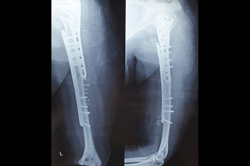

Tibia Nailing